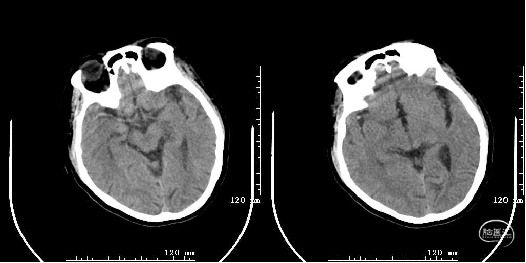

头颅CT:多发性腔隙性脑梗死,脑白质变性,右侧大脑中动脉高密度征?

头颅MRI+DWI+MRA:右侧额颞叶及侧脑室旁急性脑梗塞,右侧大脑中动脉闭塞?右侧颈内动脉破裂孔段狭窄?